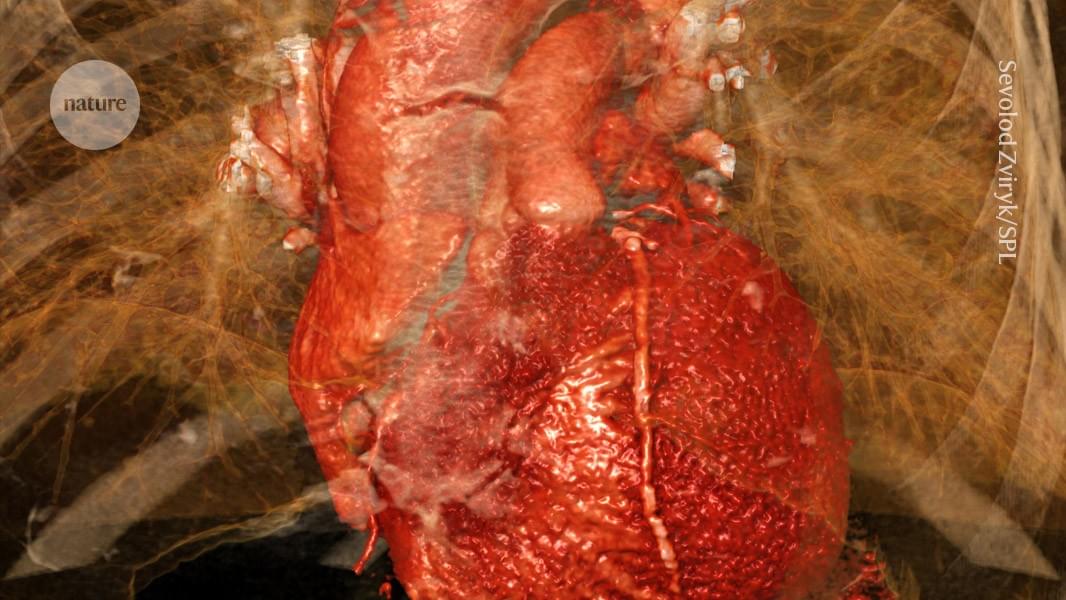

Larrinaga & colleagues discovered how a heart muscle protein fine-tunes muscle contraction by acting like a “leaky cap” & controlling how important muscle fiber components (actin filaments) grow. Learn how disrupting this control causes actin filaments to grow unusually long, perturbing the beating of the heart at.